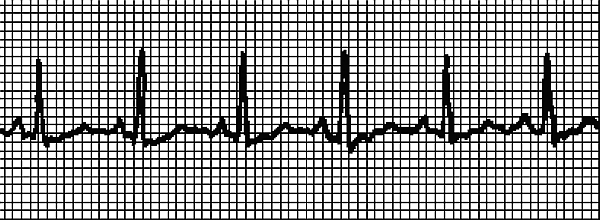

На рис. 2 записан нормальный синусовый ритм, на рис. 3 ритм при синусовой тахикардии. ЭКГ записывали у одного и того же человека сначала в состоянии покоя, затем после нагрузки. Даже не имея медицинского образования, можно понять, что существенных изменений в работе сердца не произошло – только учащение сокращений.

На рис. 4 записана несинусовая тахикардия. Водитель ритма смещен в предсердие. Если такая тахикардия легко устранится, то причина может быть не связана с болезнью сердца.

Рис. 5 должен впечатлить тех, кто злоупотребляет алкоголем, антидепрессантами, много курит или забывает, что несколько чашечек кофе на фоне усталости – это сильнодействующее средство. Скрытая до времени болезнь сердца в сочетании с этими коварными пристрастиями приводит к желудочковой тахикардии, которая относится к аритмиям, вызванным нарушениемфункциивозбудимости (см. ниже Возбудимость – еще одна функция сердца). Насколько далек такой сердечный ритм от нормального, заметит даже ребенок! Однако будем справедливы, и скажем, что в ряду причин, которые провоцируют желудочковую тахикардию, стоят также дефицит (или избыток) калия, длительное кислородное голодания по разным причинам, органические поражения сердца, длительный прием сердечных гликозидов и других антиаритмических средств, прием психотропных лекарственных средств.